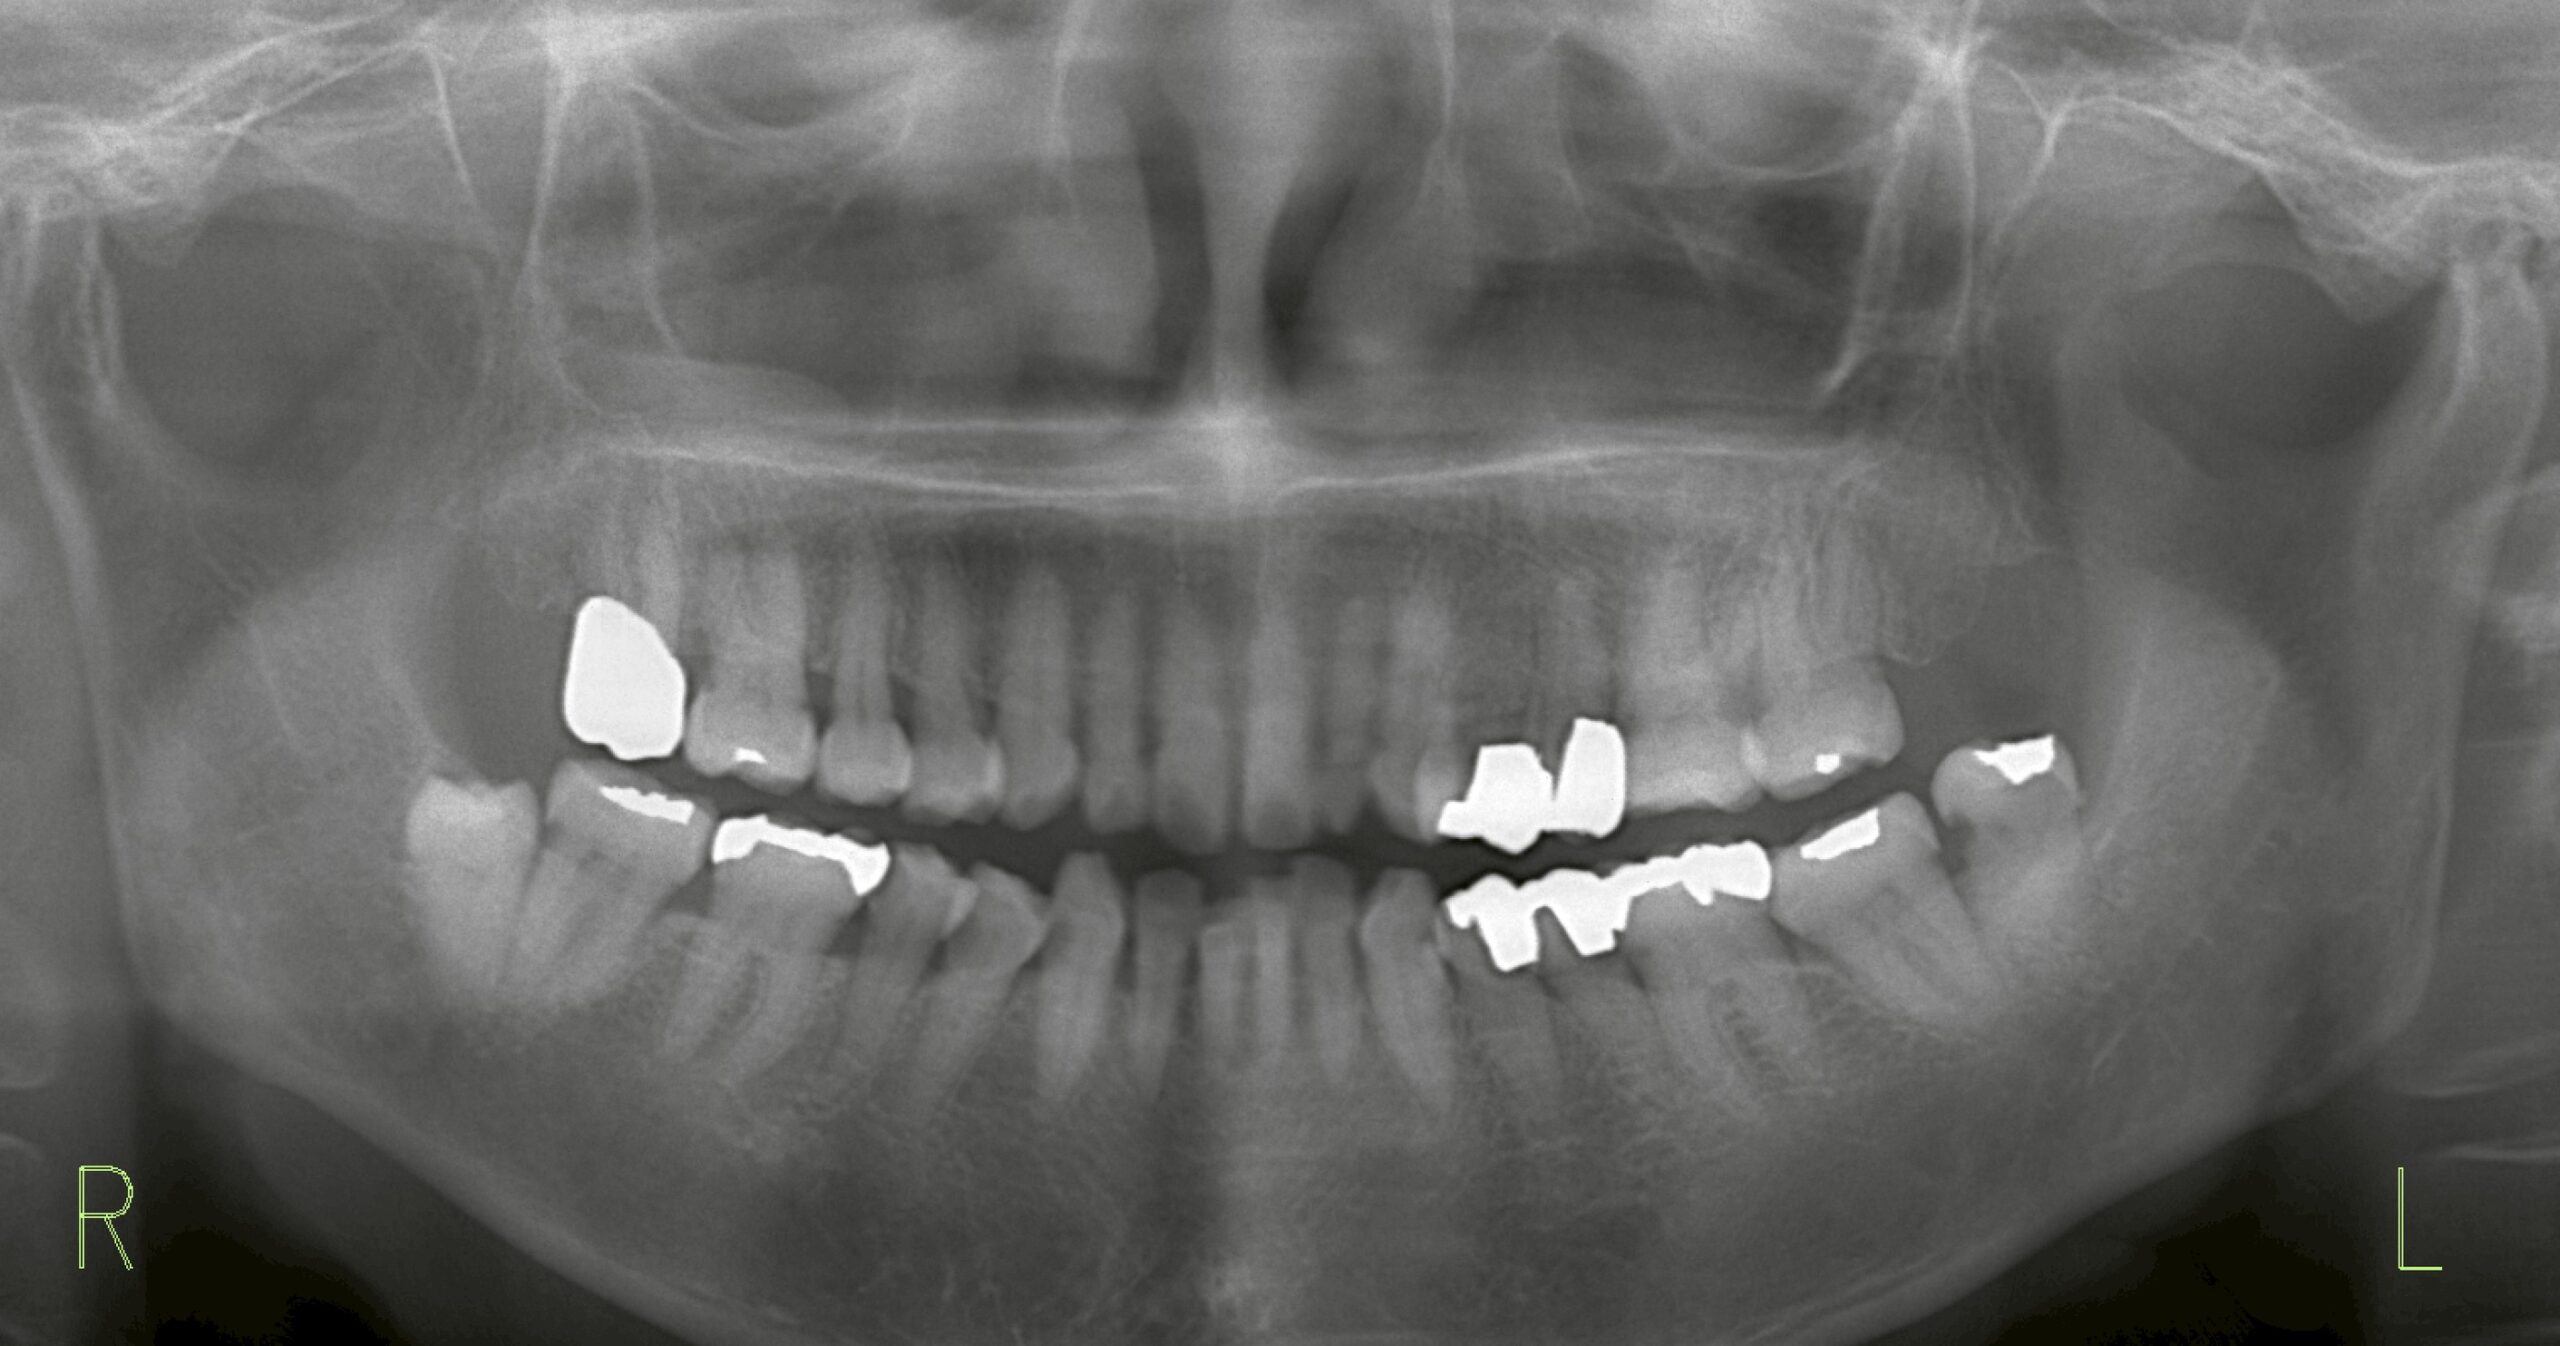

レントゲン所見

レントゲンでは左下の親知らずに 虫歯 を認め、さらにその後方には歯石が顕著に付着していました。

しみる原因として最も疑われるのは、この親知らずの虫歯です。

垂直に生えている親知らずであっても、口が開かないとブラッシングが届かず、結果的に虫歯や歯周病にかかってしまいます。